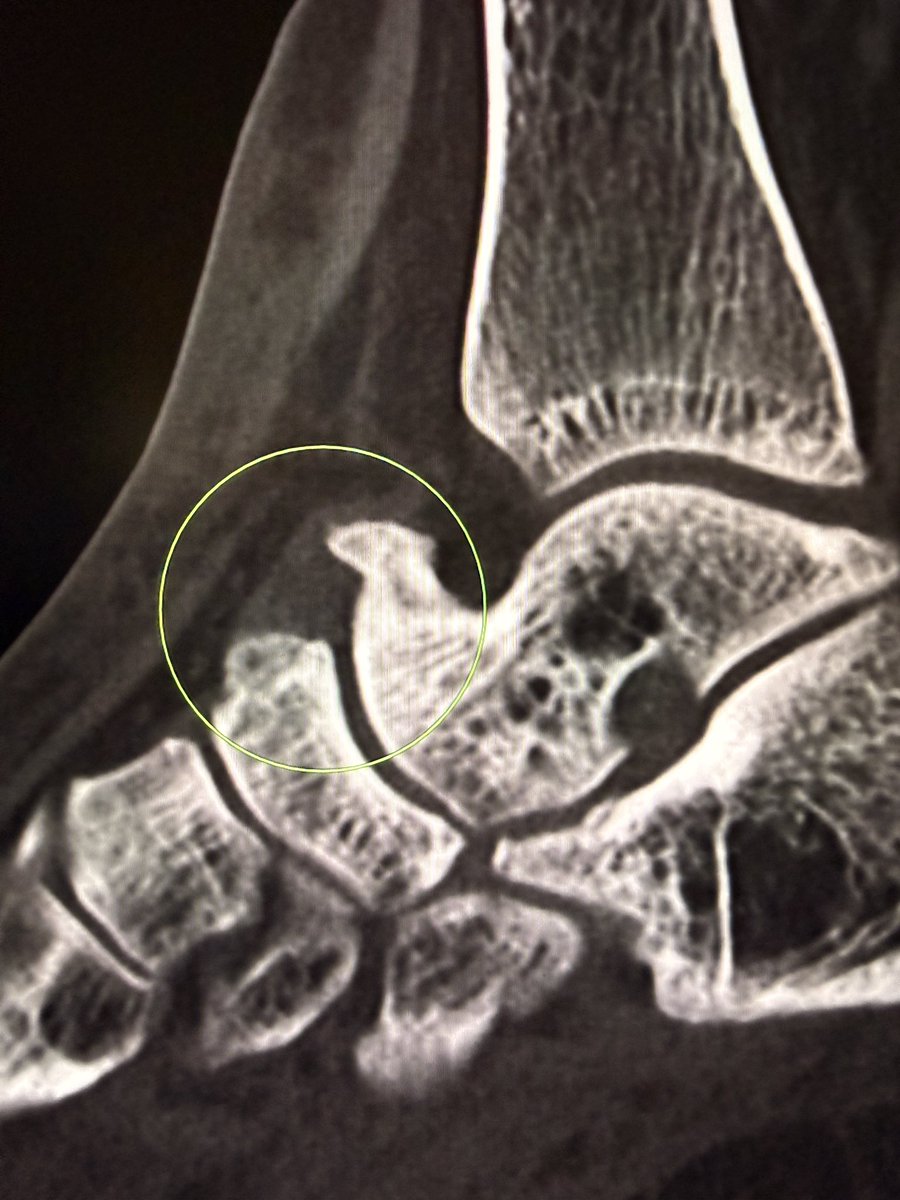

A large dorsal talar beak on sagittal CT or lateral ankle radiograph.

Talar beak is a marker of restricted subtalar motion, not a diagnosis. In a young patient, actively search for a subtalar coalition.

Wisdom: A talar beak should trigger a search, not end it.